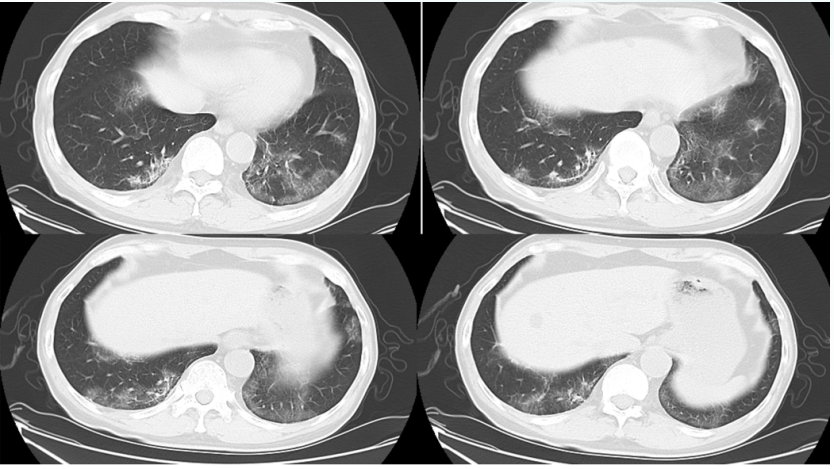

• 肺部CT: 双肺弥漫对称性磨玻璃(图1)

1  患者急诊胸部CT(2020-06-18)